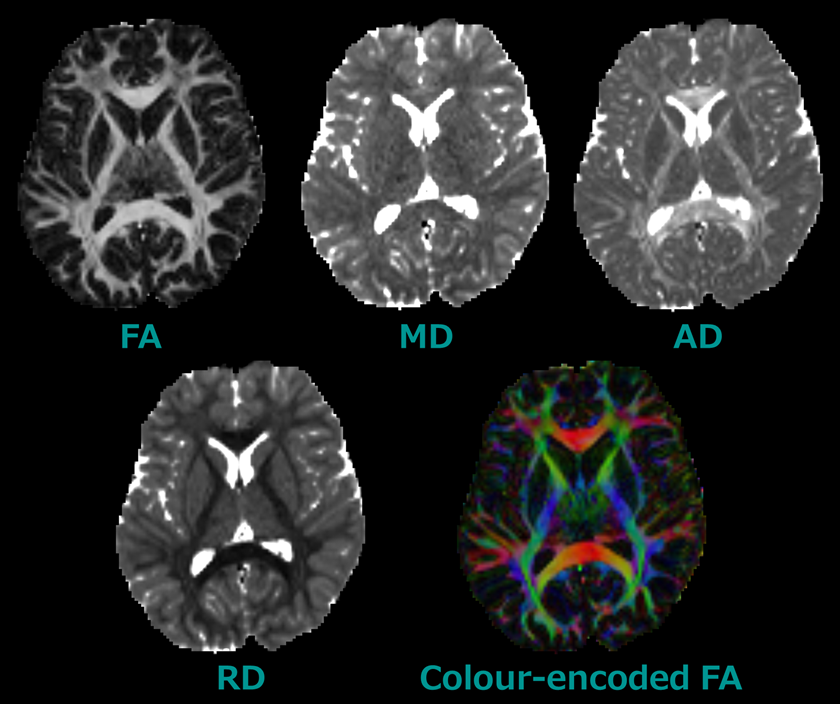

某メーカー to Introduction Diffusion 9780444528285 Imaging: Tensor 医学一般

某メーカー to Introduction Diffusion 9780444528285 Imaging: Tensor 医学一般

Introduction to Diffusion Tensor Imaging: 9780444528285,

Introduction to Diffusion Tensor Imaging: 9780444528285, Diffusion Tensor Imaging: A Practical Handbook | Request PDF,

Diffusion Tensor Imaging: A Practical Handbook | Request PDF, MRtrix】 MRtrixを用いた拡散テンソルイメージング: DTI | K-Lab,

MRtrix】 MRtrixを用いた拡散テンソルイメージング: DTI | K-Lab, The open diffusion data derivatives, brain data upcycling,

The open diffusion data derivatives, brain data upcycling, Diffusion MRI, also referred to as diffusion tensor imaging

Diffusion MRI, also referred to as diffusion tensor imaging洋書 Principles of Internal Medicine 医学書